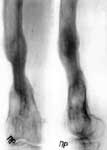

1.Последствия гематогенного остеомиелита правого бедра.